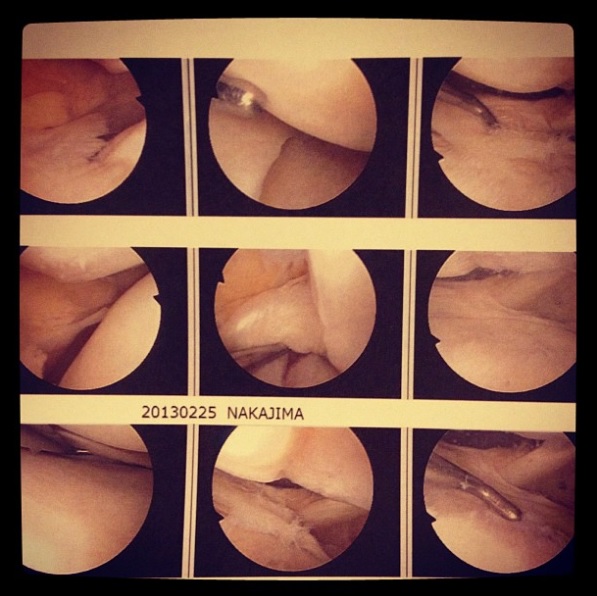

で、内視鏡の写真を見ながらいろいろ先生に状況を説明されました。

「左側外側、半月板すべて無いです。それどころか、軟骨も超えて骨まで上下すり減ってます。よく普通に生活できてますね。」

半月板損傷くらいは予想してたんですが、すっからかんになっているとは思いませんでした。

写真見ながら説明されると、「はい、まさにそこが痛いんです。」って感じで中身が見えてすっきりした感じはありましたね。

それで、関節の上の骨の部分に削れてできた溝があるのですが、そこに下の骨が引っかかってトリック中にギアが外れたようになっていたようです。